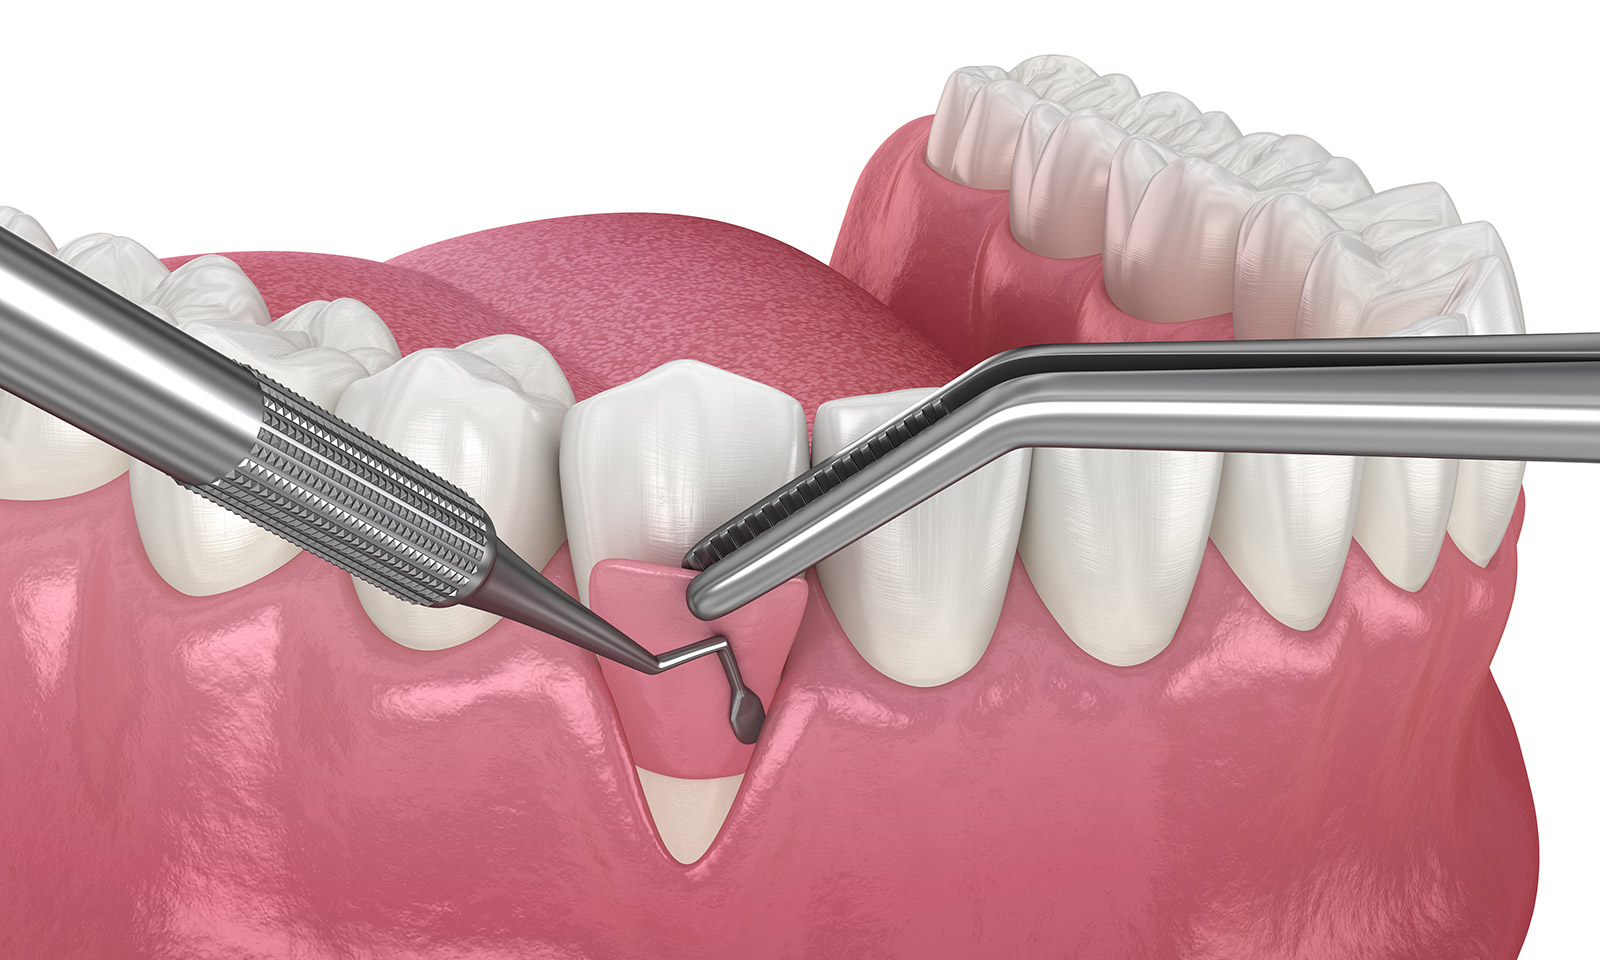

奥底の歯石を取り除く「歯周外科治療」

歯周病が進行し歯周ポケットが深くなると、通常の方法では歯石を取ることができません。放置すると歯周病はさらに進行し、いずれ歯が抜けてしまいます。そこで、歯肉を外科的に切開するなどの方法で、奥底にこびりついた歯石を取り除く「歯周外科治療」を行います。

FOP法

「FOP法」は、歯周ポケットの奥底に溜まった歯石を取り除く治療法です。歯茎を切り開き、歯石を取り除いてから縫合します。歯石や汚れを取り除くと炎症が回復し、歯周ポケットは徐々に浅くなります。